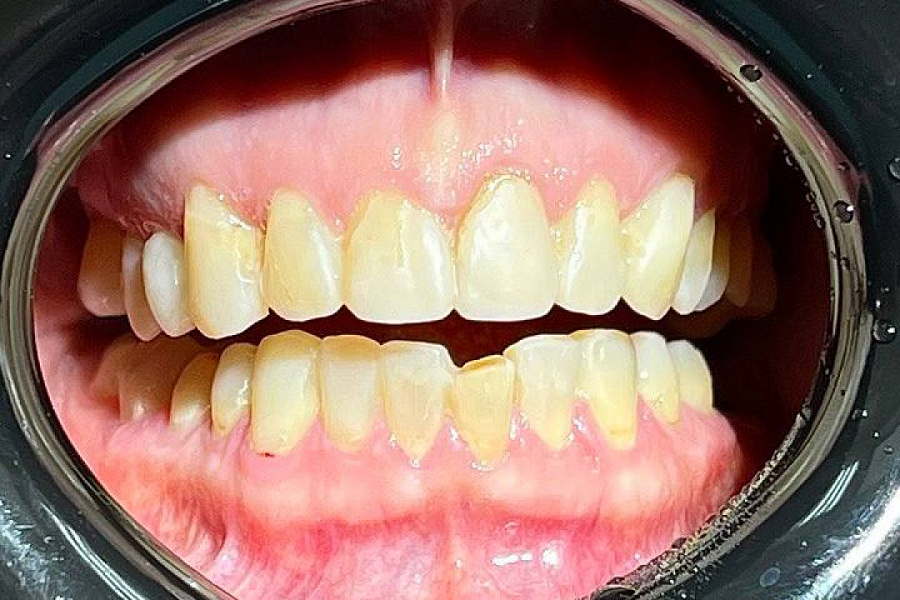

Пациентка обратилась с жалобами на неудобство и дискомфорт в области суставов. Диагностика выявила, что проблема связана с некачественным лечением и протезированием, которое вызвало снижение сустава нижней трети лица и изменение позиции других элементов ВНЧС.

1. Изготовили 3D-модели в новой терапевтической высоте.

2. Провели санацию зубов.

3. Далее сделали примерку будущих конструкций и на основании прототипа выполнили тотальное протезирование в новой терапевтической высоте в центральном соотношении челюстей.

После чего суставы встали в правильное положение, ушел дискомфорт при жевании, а лицо стало более подтянутым (антиэйдж стоматология в действии!)

Пациентка выбрала цвет зубов, который значительно светлее её естественного цвета. Но в результате всё смотрится очень натурально.